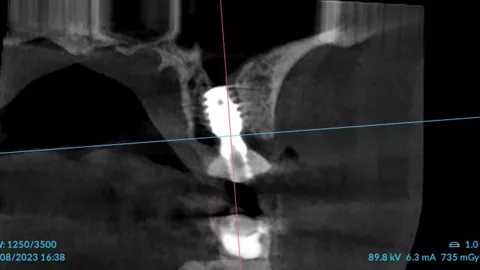

3a. 3b. 3c. 3D volumetric diagnosis and planning of implant therapy.

3a

3b

3c

4. Radiograph exhibiting a suitable septum for immediate implant placement.

4

10a. 10b. 10c. 3D scans and radiograph control of the implantplacement.

10a

10b

10c